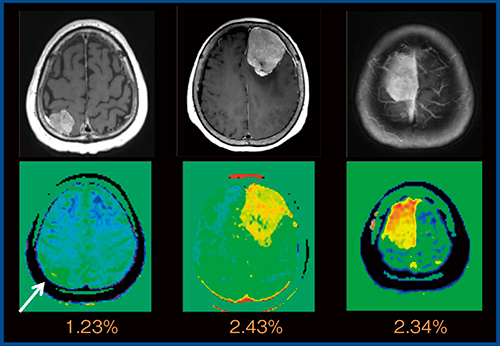

さらに,神経膠腫とリンパ腫の鑑別として,high gradeの神経膠腫の方がCEST効果が高いことが報告されている3)。髄膜腫の良悪性鑑別についても,悪性の異型性髄膜腫の方がCEST効果が高いことが報告されている4)。当院でAPT CEST imagingを実施した3例の髄膜腫(WHO gradeⅠ)においては,1例はCEST効果が低く,2例は高い結果であった(図6)。

図6 Meningioma(WHO gradeⅠ)のMTRasym_3.5ppm map